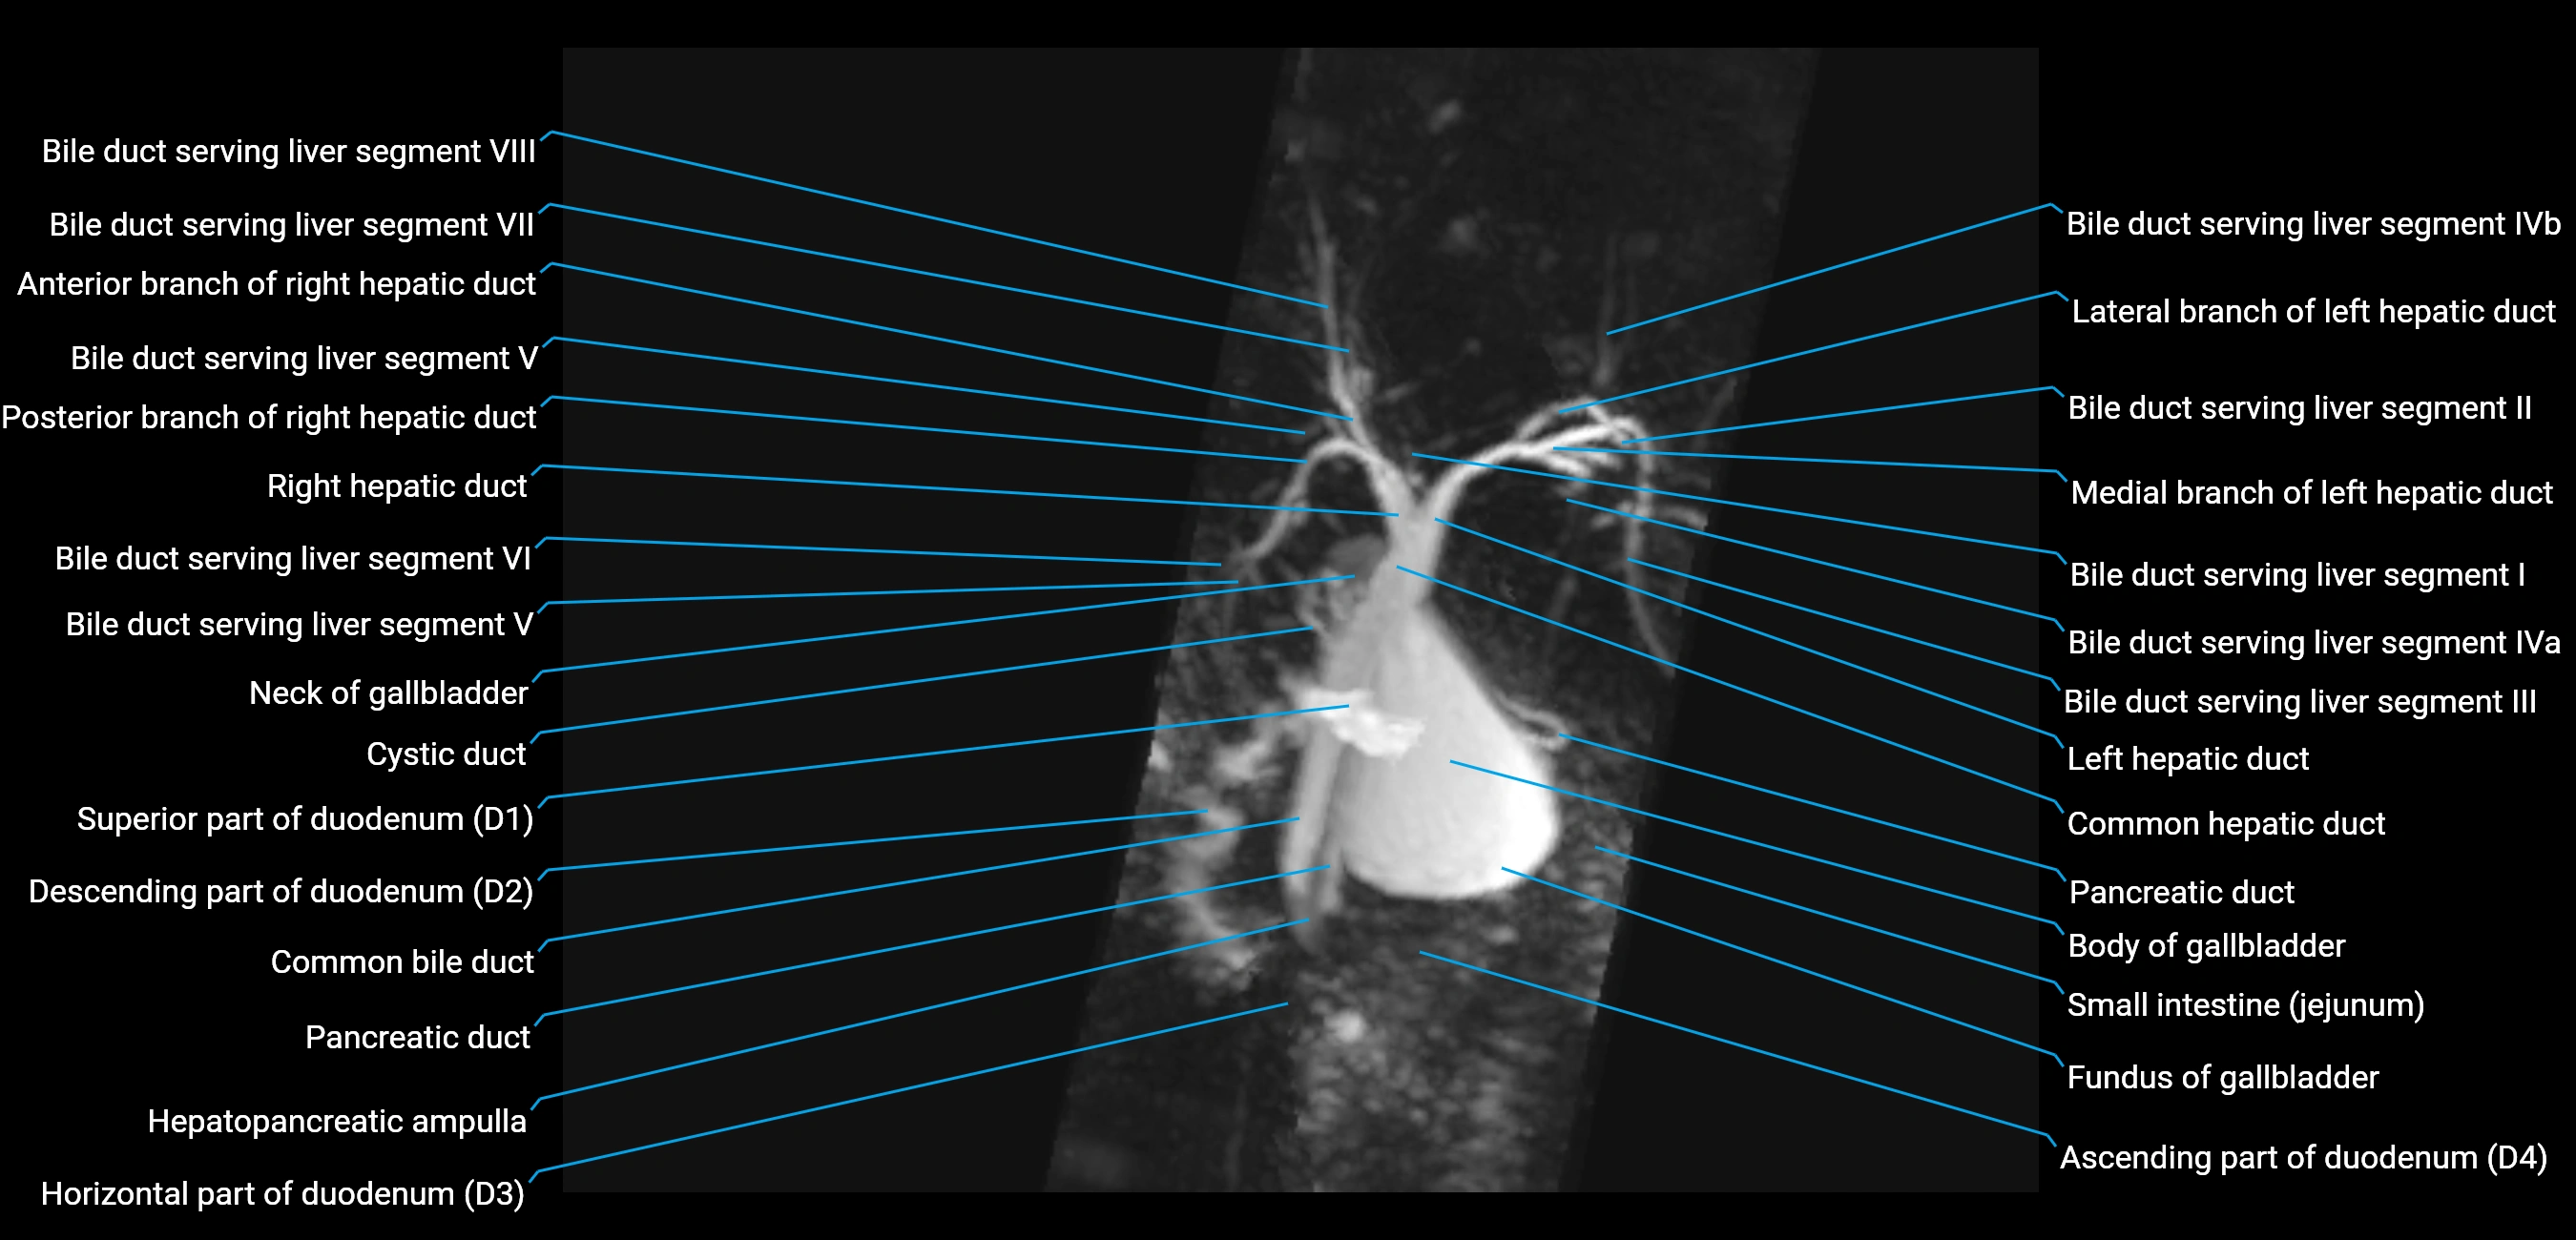

T2 TSE Fat-Saturated 3D (MRCP sequence):

• Duct visualized as a continuous bright tubular structure joining or parallel to the main pancreatic duct

• Allows 3D reconstruction of ductal anatomy and variants

• Excellent for diagnosis of pancreas divisum

Thick-slab T2 Fat-Saturated HASTE:

• Shows the accessory duct as part of the biliary–pancreatic system in a projectional image

• Highlights communication with main pancreatic duct and opening into the minor papilla

• Filling defects (stones, strictures) seen as dark spots within bright fluid

MRI image

image